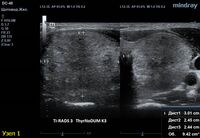

4) Узел правой доли, не прорастает капсулу щитовидной железы (0 баллов), больше широкий чем высокий (0 баллов), не имеет кальцинатов (0 баллов), с ровным четким контуром (0 баллов), изоэхогенный (1 балл), смешанной структуры (кистозно солидный) (1 балл). Количество баллов 2, ACRTi-RADS2, ThyrNoDUMК1. Пункция не показана в связи с низким риском.